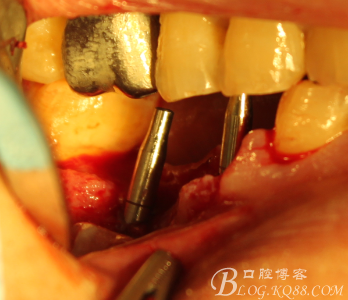

翻瓣,拔除C5,跟尖端有吸收

徹底搔刮肉芽,定點(diǎn),正對(duì)顎尖,擴(kuò)孔同期行慢轉(zhuǎn)收集自體骨

植入植體

C6頰側(cè)填入自體骨,嚴(yán)密縫合關(guān)閉創(chuàng)口

三維檢查種植體位置,方向,平行度